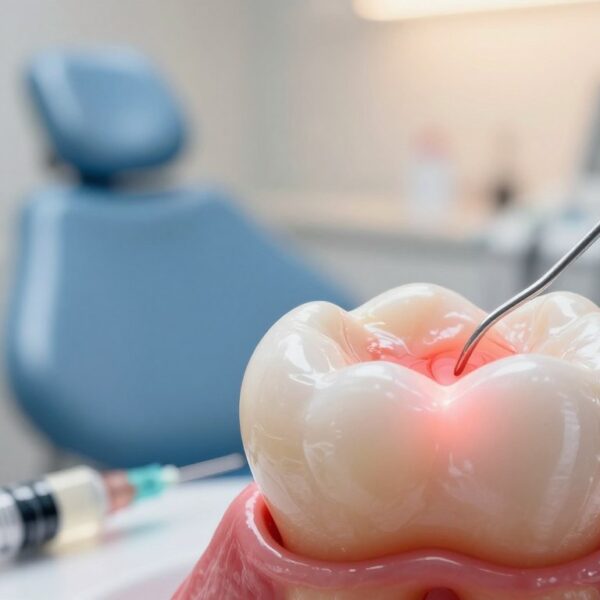

Zapalenie miazgi zęba – jak uśmierzyć ból doraźnie i kiedy potrzebne jest leczenie kanałowe

Czy nagły, pulsujący dyskomfort w jamie ustnej może być sygnałem czegoś poważniejszego? To pytanie warto zadać przy pierwszym nasileniu dolegliwości. Stan zapalny we wnętrzu zęba często daje ból samoistny, promieniujący…